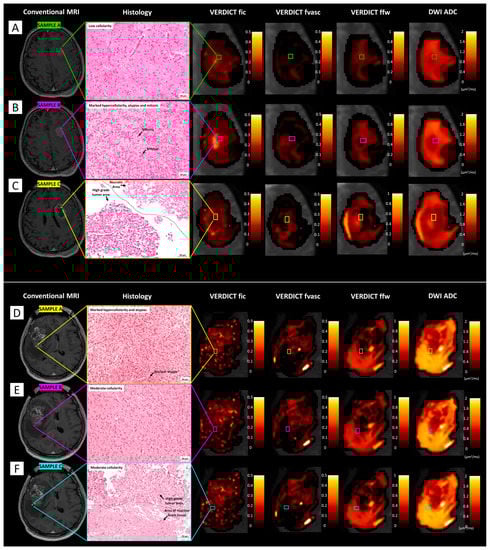

Figure 6 shows VERDICT and ADC maps and histological images from gross resection of a low-grade glioma and a metastasis. In the former case, VERDICT showed very low fic and fvasc values, compatible with the low cellularity shown by histology. In the latter case, VERDICT estimated areas of very high fic and fvasc in the core of the tumour, in agreement with the high cellularity that is typical of malignant tumours such as metastatic melanoma. The free water fraction was high in the peritumoural area (vasogenic oedema) and in some intratumoural spots that may have corresponded to necrosis. ADC maps qualitatively showed less heterogeneity across the tumour tissues.

Figure 6.

Comparison between VERDICT maps and histology from gross resection. (A) The first case (Patient 19) underwent surgical resection for a large left temporo-parietal low-grade astrocytoma (WHO 2, IDH-mutated); the histopathological section shows mild cellularity with the presence of fibrillary neoplastic astrocytes on a loose tumour matrix background; some mild nuclear atypias are identifiable. (B) The second case (Patient 4) underwent surgical removal for a large melanoma metastasis; histopathology shows marked hypercellularity with epithelioid cells with abundant cytoplasm, large nuclei, and prominent nucleoli interlaced with extravasated red blood cells.

Figure 7 shows VERDICT and ADC maps and histological images in multiple samples from stereotactic biopsies in two patients harbouring high-grade gliomas. In the first case (patient 12), fic values were higher in the area corresponding to sample B, with histological features of high-grade glioma, than in the area corresponding to sample A, with histopatological features of infiltrating glioma cells. In the area corresponding to sample C, fic values were very low and ffw values were the highest, corresponding to necrosis as shown by histology. In the second case (patient 3), fic values were higher in sample A than in the other two samples, compatible with the higher grade shown by histology; fvasc values were also slightly higher in sample A. In contrast, ffw values were low in sample A, intermediate in sample B, and highest in sample C, compatible with the presence of oedema.

Figure 7.

Comparison between VERDICT maps and histology from stereotactic biopsy. (A–C) The first case (patient 12) underwent stereotactic biopsy for a left frontal WHO 4 glioblastoma (IDH-1 wild-type). From a histopathological point of view, the first sample (A) was characterised by mild cellularity; the second bioptic sample (B) was performed in a higher grade tumour area, characterised by marker hypercellularity, atypias, and mitotic figures; in the third sample (C), both necrotic and high grade tumour areas were identified. Note the increase of fic values from periphery (A) to the tumour ‘vital’ core (B) and the drop in fic values and marked increase in ffw values in the necrotic core (C). (D–F) The second case (patient 3) underwent stereotactic biopsy for a right frontal WHO 4 glioblastoma (IDH-1 wild-type). Histopathologically, the first sample (D) was characterised by marker hypercellularity and atypias; the second sample (E) entailed areas of moderate cellularity; the last sample (F) showed areas of high-grade tumour adjacent to areas of reactive brain tissue with possible infiltration. Note the progressive reduction in fic values from (D) to (F), along with the increase in ffw values, possibly due to oedema.